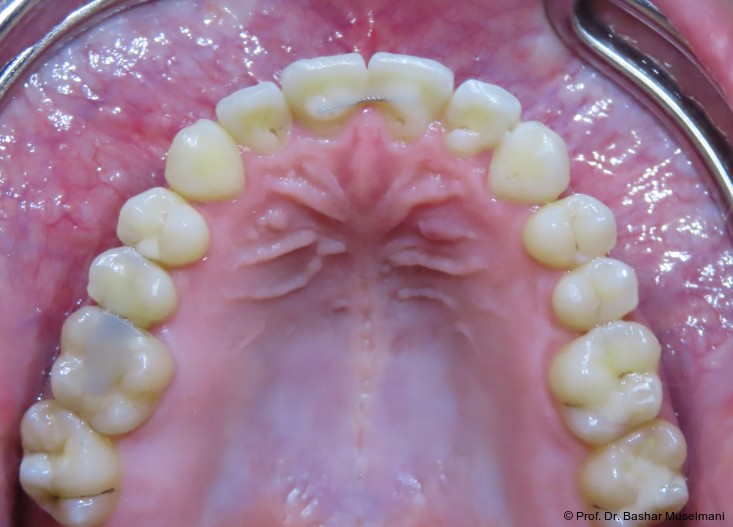

Der Patient (28 Jahre 8 Monate) stellte sich mit einer skelettalen Klasse III sowie einer Mittellinienabweichung nach links vor.

Klinische Befunde

• leicht konkaves Gesichts- und Mundprofil

• posterior positionierter Unterkiefer (VW)

• retroinkliniert stehende Unterkieferfront

Die Abbildungen 1 bis 3 zeigen die initiale klinische und radiologische Ausgangssituation.